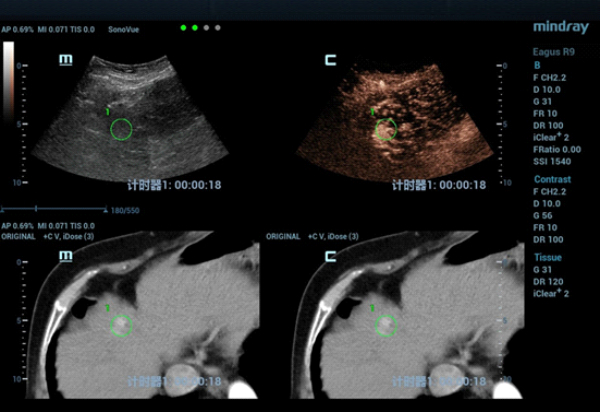

CT??? ??? S4?? ??? ??? ?? ???????? ??? ?????. CEUS(Contrast-Enhanced Ultra Sound)????? ?????? ??? ??? ??? ??? ???? ? ??? ???? ???? ??? ???????.

??? ??? ?? ????? ???(MWA)? ?? ?????? ?? ?????? ??? ???? ??? ?? Contrast-enhanced CT? ???? ??? ?? ??? ??? ?? ??? ?? ??? ????? ???? ???? ????? ??(MWA)? ??? ???????.

??? ????? ??? 2D ??? ??? ???? ???? ???? ??? ? ????? ??? ??? ?? ?????? ???? ?? ??? ???? ???? ??? ? ?????. ??? ??? ???? ??? ?? CT ??? ??? ???? ??? ??? ??? ?? MWA? ?? ???? ??? ???? ?????. CEUS(Contrast-Enhanced Ultra Sound)? ???? ?? ? ??? ??? ????, ?? ? ?? ??? ???? ?? ?? ??? ???????.?